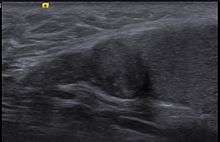

Adenomatoid tumour of the epididymis